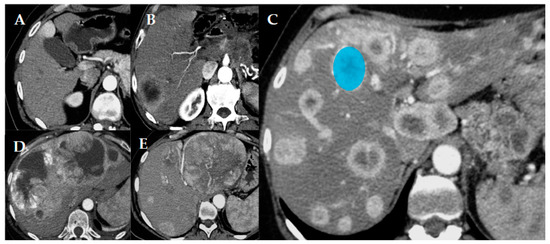

Figure 1. Different patterns of pancreatic neuroendocrine tumor (p-NET) metastatic spread in the liver. Uninodular (A), paucinodular (B), multinodular (C), confluent multinodular (D), and bulky (E). In image (C) an example of how the volume of interest (VOI; blue circle) was placed when performing the texture analysis is reported.